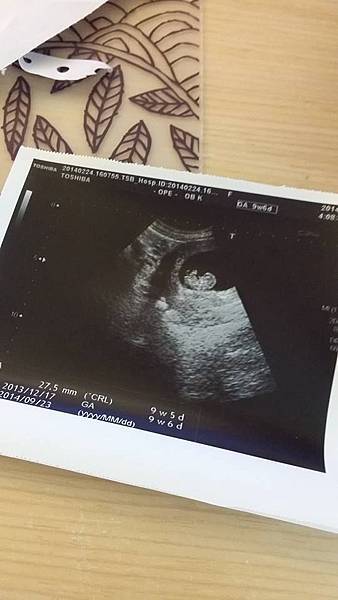

照到囉!!!!!

小寶貝著床囉~

一個小小的豆子是個小生命耶!!!

從一個小豆子~

到下次產檢看到了我的小寶貝!!!